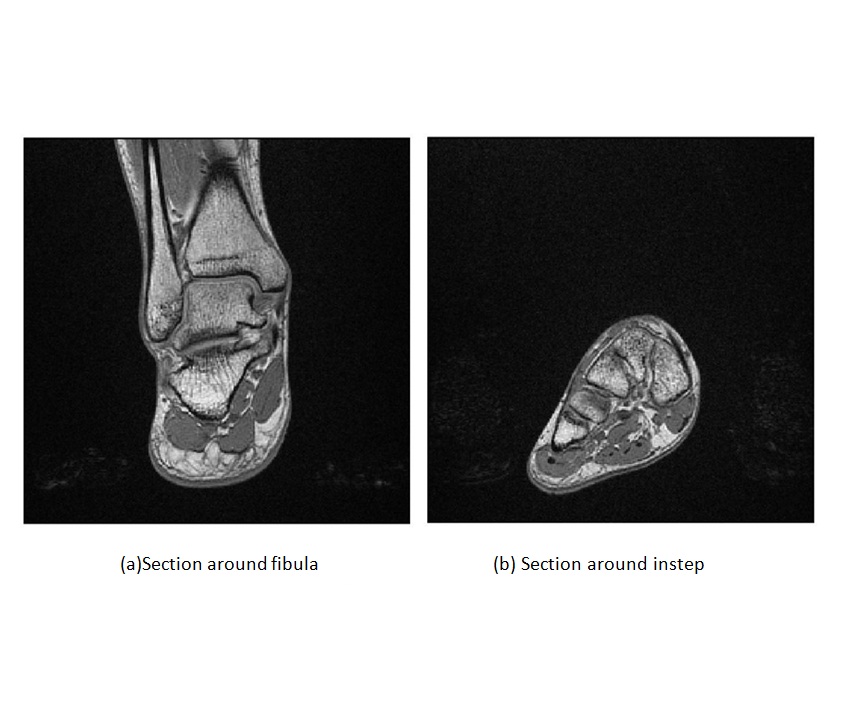

• Figure 1.13

Example of MRI images